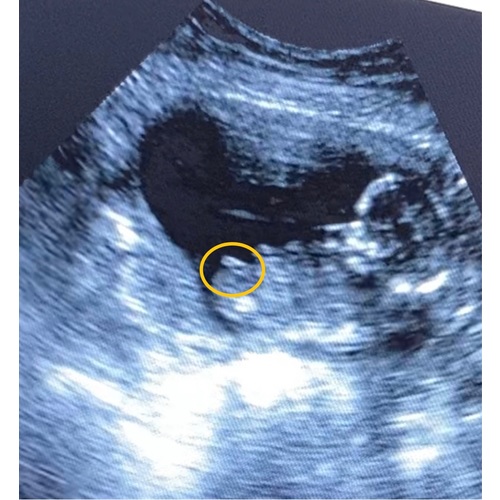

Dit is alles wat ik kon zien, maar geen idee wat het dan is 😅

Ik denk een jongetje